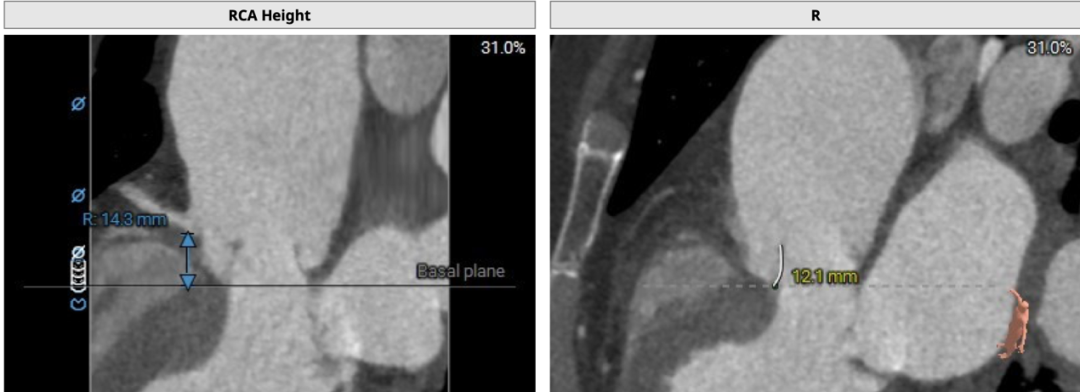

左侧冠脉开口高度低,LCA 9.8mm,左冠瓣瓣叶长度约12.8mm;右侧冠脉开口高度可,RCA 14.3mm:

术中建议造影角度RAO 7°,CAU 14°(其它参考角度如下图):